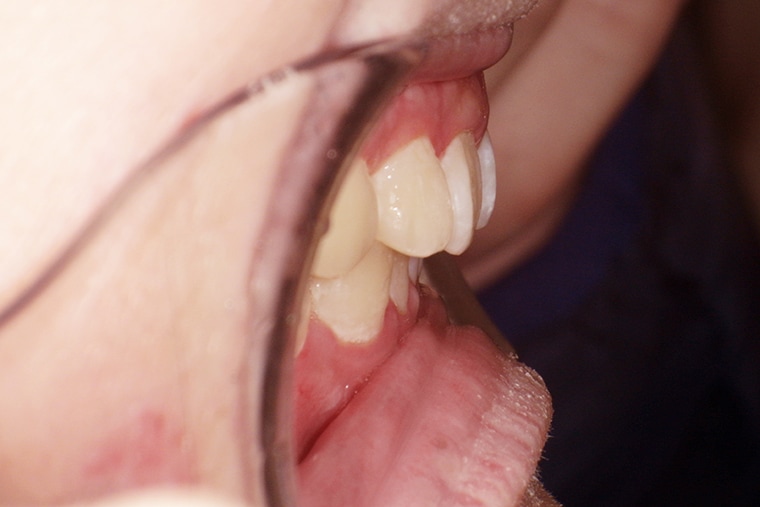

BEFORE